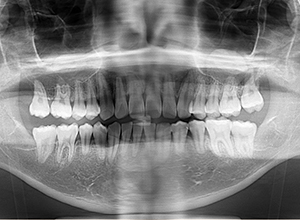

X-Ray

X-Ray所見

セファロ所見 下顎 頭はやや後方に位置しており、下顎枝の長さに対して骨体部は大きく、下顎角は開大しているためハイアングルを呈していた。中顔面部の高さは高く奥行きもあった。前後的にはII級の骨格形態を示していた。